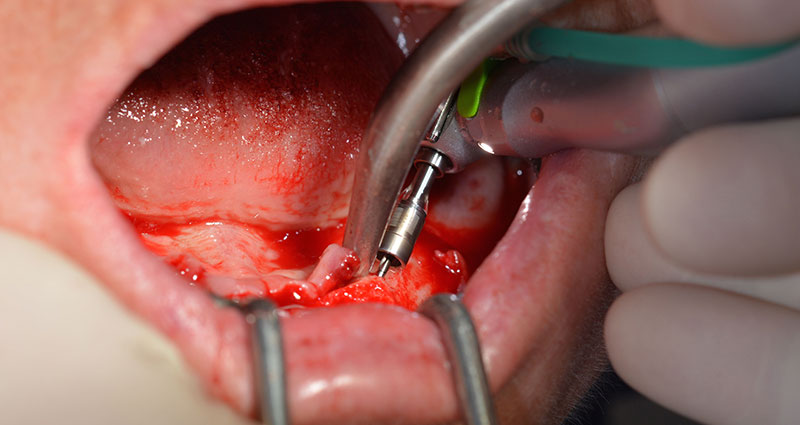

Tras la extracción de la dentición residual en el maxilar inferior, se realizó la incisión crestal en la región comprendida entre la pieza dental 37 y la 47.

A continuación, se identificó el agujero mentoniano (foramen mentale) como la estructura anatómica límite y se alisó el cortical de la cresta ósea con la pieza de mano recta y una fresa redonda grande (fig. 4).

El protocolo quirúrgico de los implantes utilizados (SKY, bredent medical) prescribe una velocidad de 1 200/rpm para las perforaciones piloto (figs. 7-9).

Fig. 7

velocidad de 1 200/rpm

Fig. 8

Fig. 9

Este valor se corresponde con la posición siguiente del ajuste predefinido en Implantmed. Aquí se aprecia la inclinación de aproximadamente 45 grados del contra-ángulo de W&H hacia medio caudal en la región de la pieza 45 para preservar el nervus mentalis. El foramen mentale sirve como orientación anatómica para todas las perforaciones en esta zona. Las perforaciones siguientes se realizaron con una velocidad reducida de 300/rpm (figs. 10 y 11).